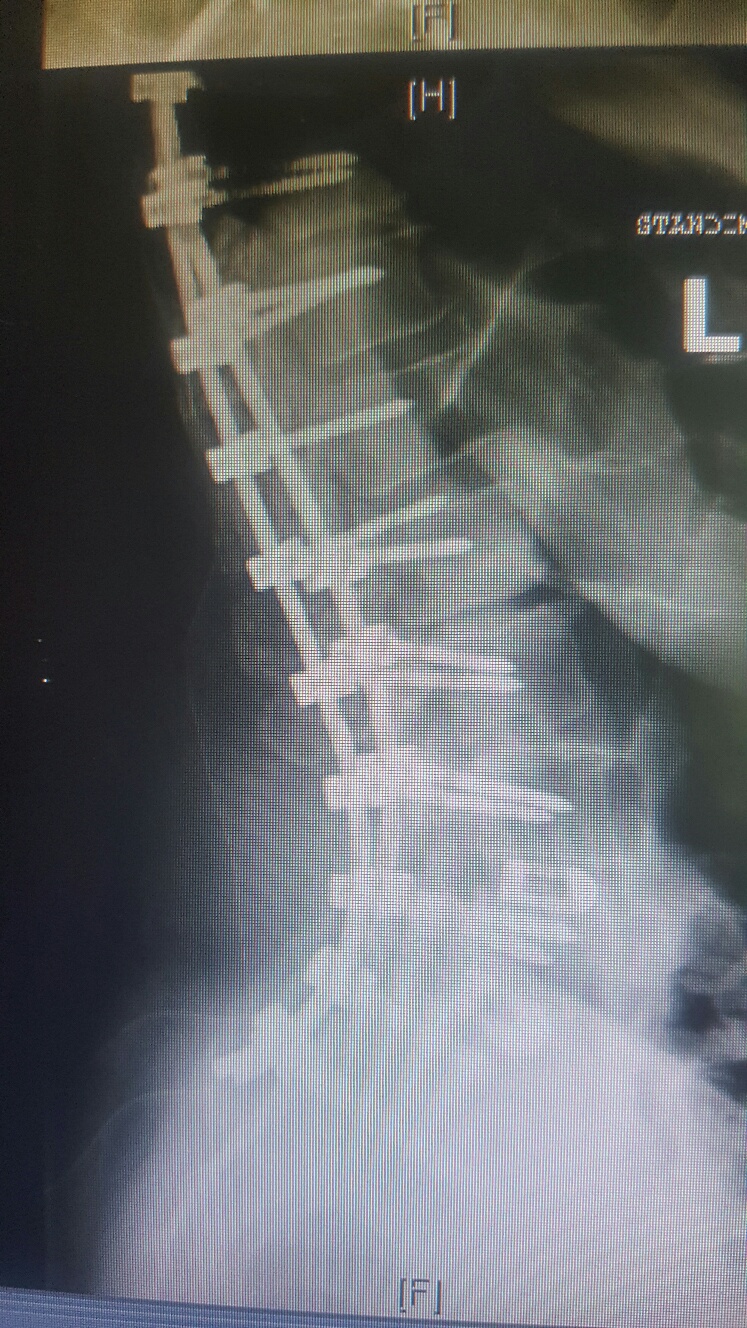

i am the bionic woman, iron woman, titanium broad, i don't know quite yet hopefully i don't break any of the rods or pull any screws...but heres the before and after xrays....

before: lateral scoliosis

lumbar spine 1 scoliosis.JPG

and rotatory scoliosis

right bending.JPG

with bad discs and bone spurs

i am pretty darned close to 0 degrees on the scoliosis!!!! and my spine isn't twisted anymore either! it feels totally different to walk, sit, stand, basically to do anything, but that's okay! the square things in the after xrays are cages to replace the discs that were removed.

been doing all my wussy stretching exercises....still feeling really timid and tender around L2, which is the one that is worst off to the left side in the first xray. they really had to crank that one back into position. i also met some very very happy medical students LOL. they thought it was "so cool and totally awesome" (quote-scary enough) that they could see a laminectomy and help put me back together again (apparently everything twisted and they needed hands to hold things in place so they're stop twisting.....um. LOL.

so they removed the backs off the vertebrae at L2 L3 L4 and L5 it looks like from the xrays. took out all the facet joints (the bars are where they would be)....so that freed up all the pinched nerve roots and took the pressure off my spinal cord.